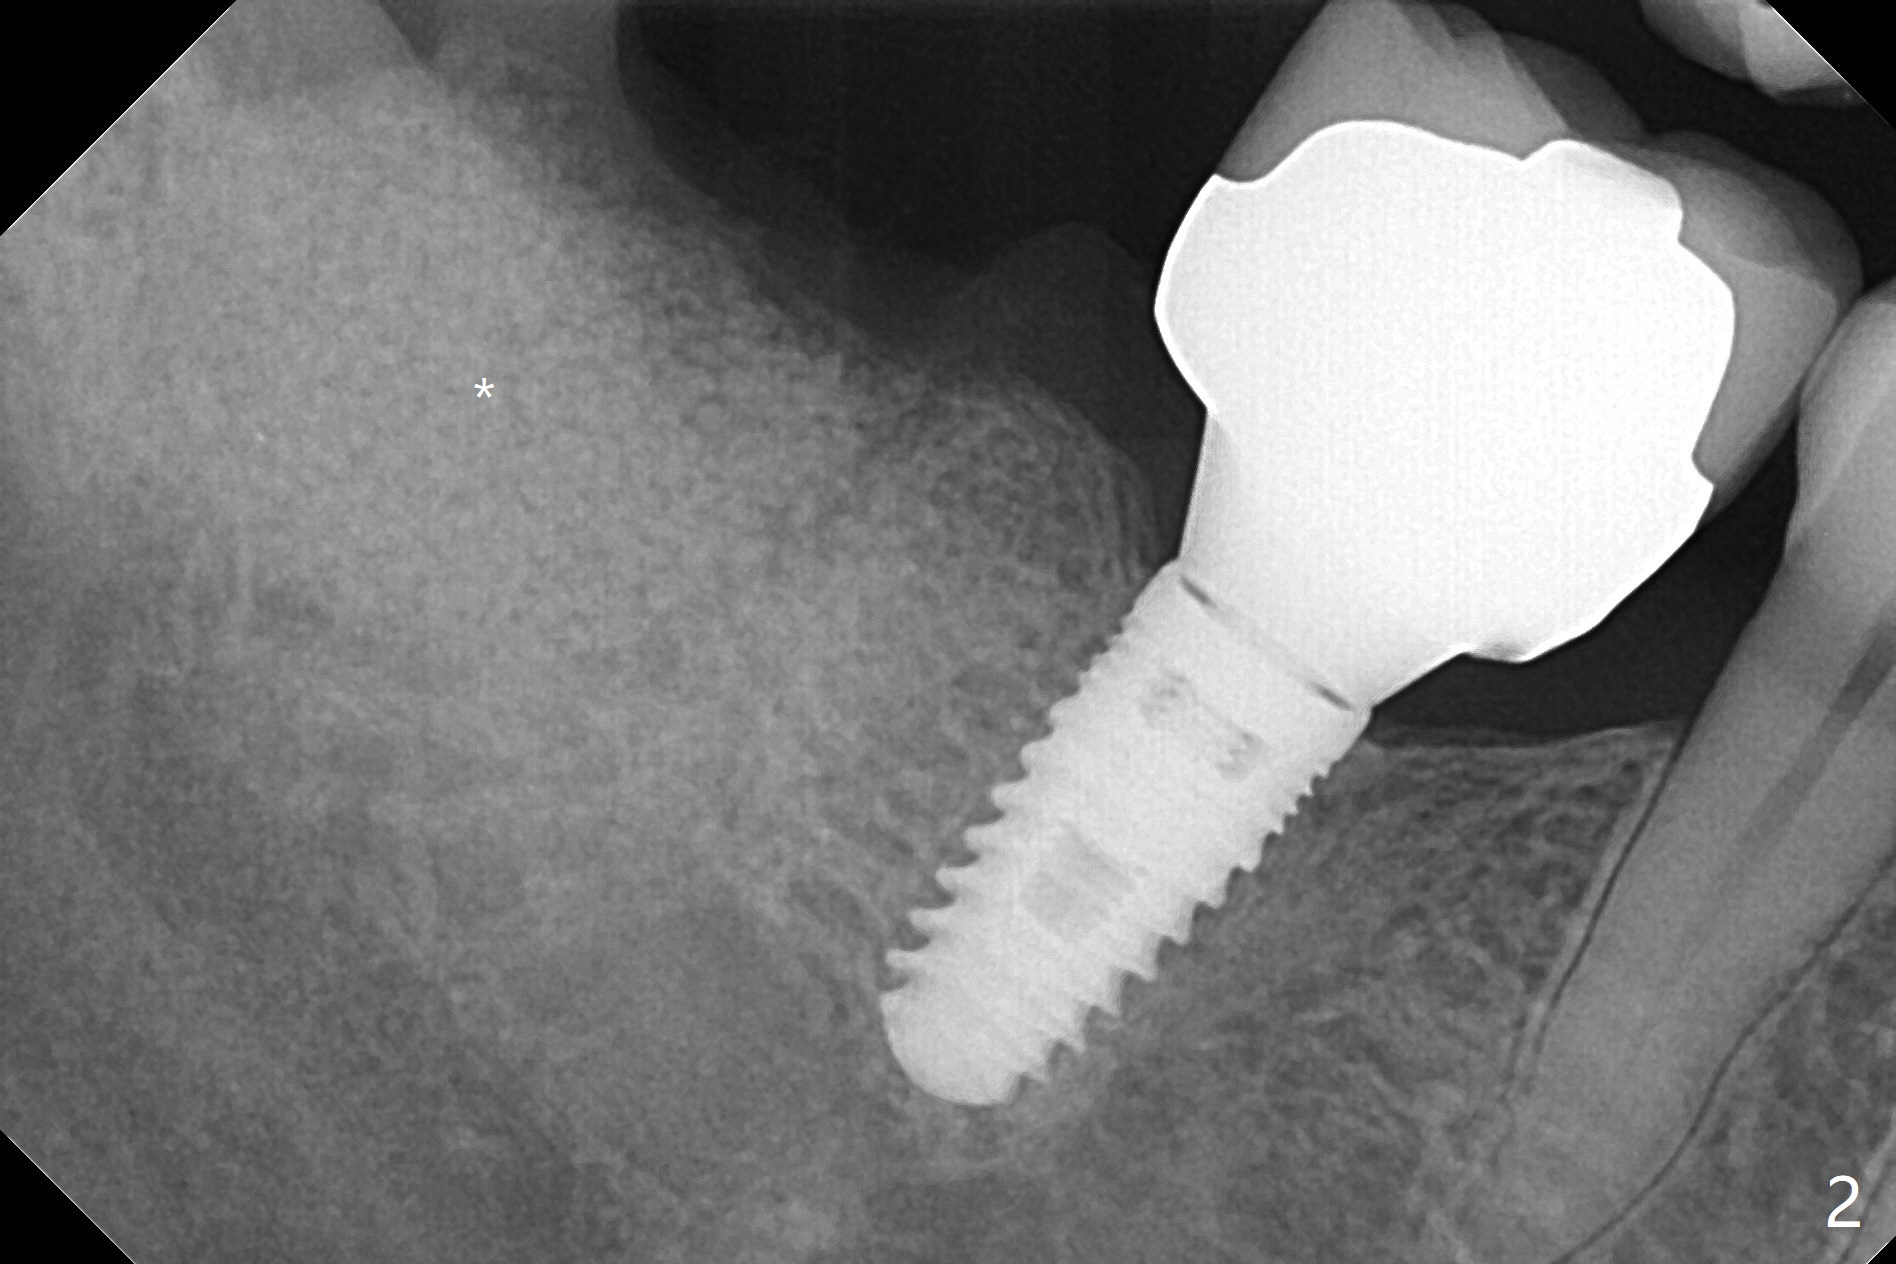

56岁男严重牙周炎,要求拔除右下7(图一),病人特别提出彻底清除炎性组织,GEM21S与皮质骨粉调袢5分钟后放置清创的牙槽窝(图二:*),覆盖Cytoplast,4-0 PTFE缝合。术后一个月膜游离(图三),撤线(缝线不是故意穿过膜)后,膜去除,下面骨粉好像稳定(图四至六)。